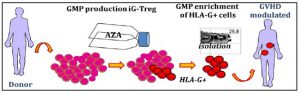

Τίτλος Ερευνητικού Έργου: «Παραγωγή καινοτόμων ανοσοθεραπειών μέσω φαρμακολογικής επιγενετικής τροποποίησης»

Επιστημονικός Υπεύθυνος: Σπυριδωνίδης Αλέξανδρος